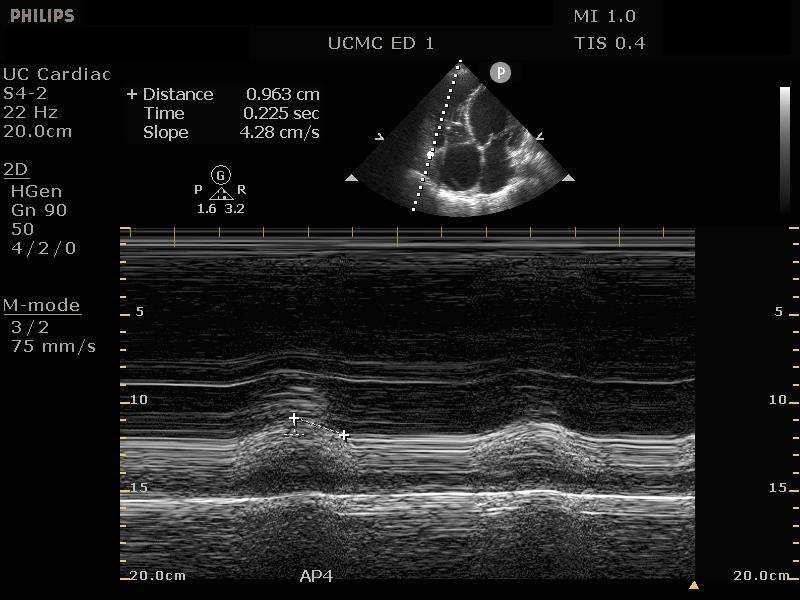

EPSS

In the parasternal long view, an M-mode line is placed through the anterior mitral leaflet. The distance is between the leaflet tip and interventricular septum is measured during the point in early diastole where the tip of the leaflet is closest to the septum. (Figure 5) A value of >7mm is highly suggestive of depressed cardiac contractility or low EF. (Figure 6) Note that this measurement is invalidated by the presence of valvular pathology or left ventricular/septal hypertrophy. This method is also not valid for assessing for hypercontractility.

Figure 5. Image of normal EPSS measurement measured from the tip of the anterior mitral valve leaflet in diastole to the interventricular septum

Figure 6. Abnormal EPSS measurement